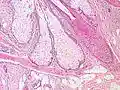

Sebaceous glands are found in hair-covered areas, where they are connected to hair follicles. One or more glands may surround each hair follicle, and the glands themselves are surrounded by arrector pili muscles, forming a pilosebaceous unit. The glands have an acinar structure (like a many-lobed berry), in which multiple glands branch off a central duct. The glands deposit sebum on the hairs and bring it to the skin surface along the hair shaft. The structure, consisting of hair, hair follicle, arrector pili muscles, and sebaceous gland, is an epidermal invagination known as a pilosebaceous unit.[3]

Base of pilosebaceous unit

Insertion of sebaceous glands into hair shaft